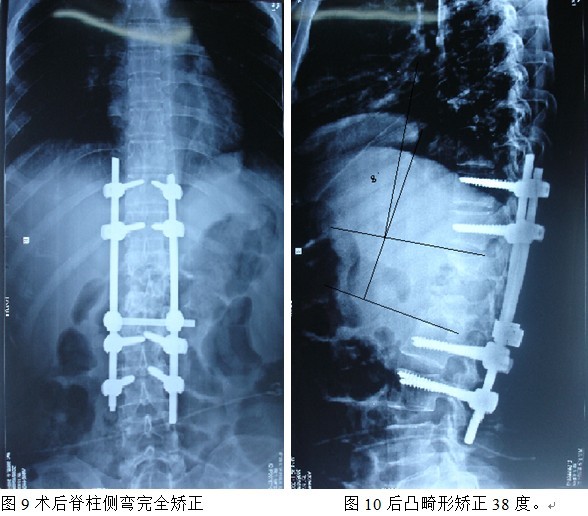

结果: 术后所有患者均显示,骨性融合, 马尾神经损伤的患者均基本恢复正常,术后后凸畸形平均矫正90%以上, 3-49个月的随访,后凸角度平均丢失4.2°。

本组手术用时间3~4h , 平均3.5h 。术中出血300~500ml , 平均约350ml 。术后症状完全缓解,无神经功能障碍加重等并发症,1例营养差的老年患者伤口出现窦道,1例因肝功能差,术后未口服抗痨药,伤口出现窦道,经换药后二期愈合,其余病例伤口均一期愈合。马尾神经受损的患者术后基本恢复正常。术后一周后凸角平均 5.4°后凸畸形平均矫正90%以上, 最终后凸角平均8.3°,后凸角度平均丢失4.2°。随访3个月有87%(40/46)有骨痂形成,6个月91.3%(42/46)明显骨性愈合(见图),其余4例9-12个月内愈合,随访时间3-32个月,平均11个月,46例患者中2例在术后2个月和3个月时背部形成脓肿,换药后治愈。2例出院1月后并发结核性脑膜炎,治疗后好转。1例因椎弓根钉偏外,刺激神经根,5个月后从侧方脱出,疼痛加重,因前后路植骨完全愈合,取出后症状完全缓解。

中国学者金大地[22]等采用一期前路病灶清除植骨前路钢板固定治疗腰椎结核,平均18°的后凸畸形得以矫正,Mukhtar[23] AM等采用前路病灶清除植骨分期或同期后路固定治疗腰椎结核22例,术后后凸畸形矫正度数平均为27°。从我们的随访结果看,术后后凸畸形平均矫正度数为26.9°,后凸畸形平均矫正90%以上, 6个月-49个月后随访,后凸角度平均丢失4.2°。本术式也适用于结核所引起的弹性差的后凸畸形,对于病灶纤维化或骨化的非弹性后凸畸形,后路固定后,先行前路病灶、纤维化或骨化切除、松解,逐步刮除病灶、逐步撑开,达到畸形矫正和植骨的目的。